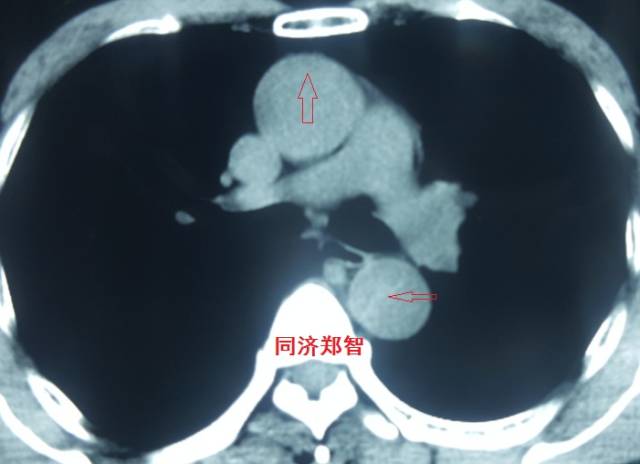

病例五

平扫CT提示主动脉弓层面及右肺动脉层面均可见主动脉血管腔内的内膜片影(红色箭头所示),CTA显示为A型主动脉夹层。